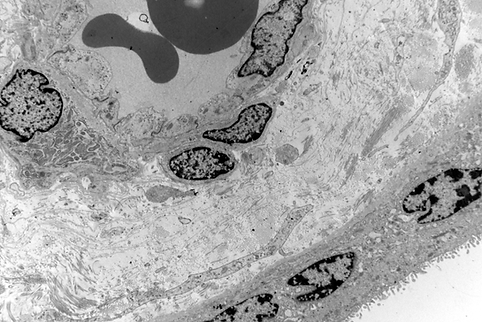

Placenta is a peer-reviewed scientific journal that publishes high-quality original research and invited reviews on all aspects of human and animal placentation. Its scope includes maternal–fetal interactions, fetal development, genetics and epigenetics, stem cell biology, molecular and cellular mechanisms, transport, immunology, pathology, pharmacology,

and developmental programming. The journal welcomes studies on implantation, endometrial function, comparative placentation, uterine and umbilical circulation, relationships between fetal and placental growth, and clinical conditions involving abnormal placental development or function. Research on placental membranes, paternal influences on placental biology, and biomarkers of placental disorders is also encouraged. Placenta is the official journal of the International Federation of Placenta Associations and is dedicated to supporting the scientific community through the rapid and rigorous processing of manuscripts.